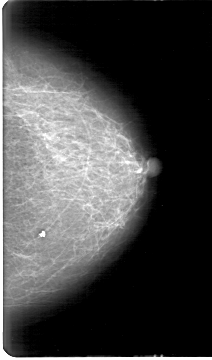

D_4170_1.LEFT_MLO

LEFT_MLO LINES 5281 PIXELS_PER_LINE 3421 BITS_PER_PIXEL 12 RESOLUTION 43.5 NON_OVERLAY